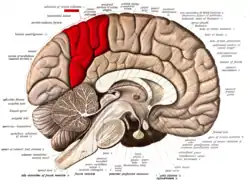

Medial surface of left cerebral hemisphere. (Precuneus visible at top left.) (Anterior to the right.) | |

In neuroanatomy, the precuneus is the portion of the superior parietal lobule on the medial surface of each brain hemisphere. It is located in front of the cuneus (the upper portion of the occipital lobe). The precuneus is bounded in front by the marginal branch of the cingulate sulcus, at the rear by the parieto-occipital sulcus, and underneath by the subparietal sulcus. It is involved with episodic memory, visuospatial processing, reflections upon self, and aspects of consciousness.

The precuneus is located on the inside between the two cerebral hemispheres in the rear region between the somatosensory cortex and forward of the cuneus (which contains the visual cortex). It is above the posterior cingulate. Following Korbinian Brodmann it has traditionally been considered a homogeneous structure and with limited distinction between it and the neighboring posterior cingulate area. Brodmann mapped it as the medial continuation of lateral parietal area 7.

Precuneus of left cerebral hemisphere (shown in red). Medial surface of left cerebral hemisphere. (Precuneus visible at top left.)

Medial surface of left cerebral hemisphere. (Precuneus visible at top left.) Medial surface of left cerebral hemisphere. (Precuneus colored in red.)